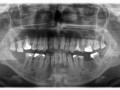

Błędy diagnostyczne oraz techniczne w leczeniu…

Aneta Neskoromna, Aneta Mamos, Dawid Zagaki